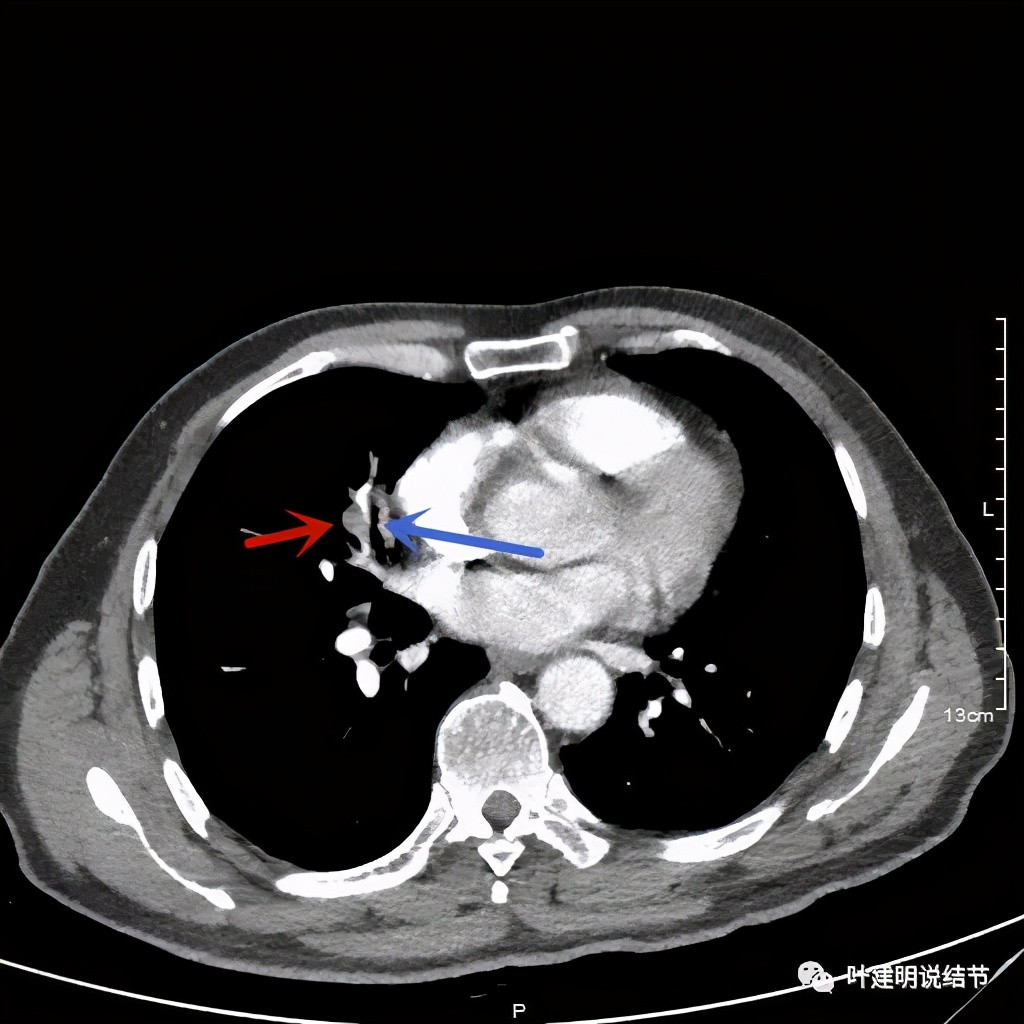

上图示病灶实性,且粉色箭头所示处边缘不平整,似细毛刺征(不太典型),蓝色箭头示像支气管截断(肿瘤堵塞的样子,但后文中有气管镜下未见异常,那么可能是角度的关系)